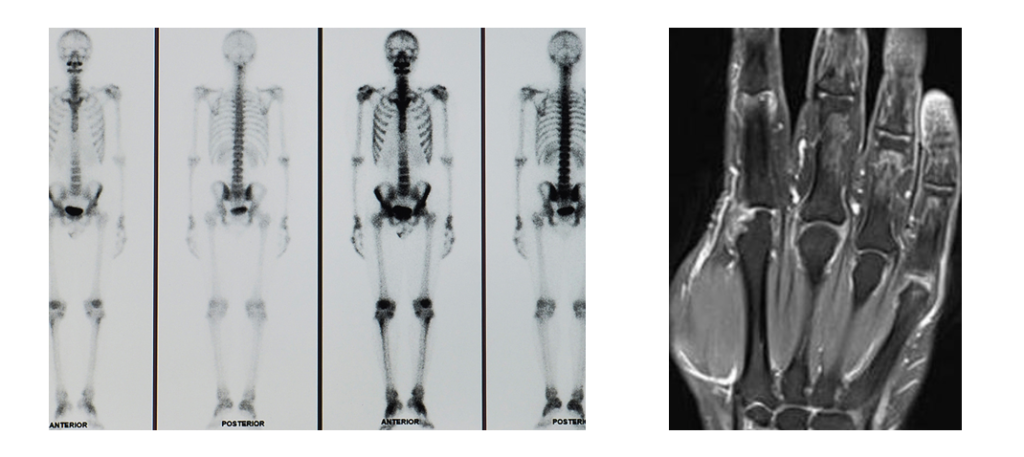

Gli accertamenti principali che danno riscontro della malattia sono la scintigrafia ossea e la risonanza magnetica.